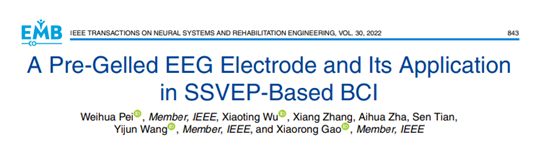

图1:PreG电极示意和实物图

如图1(a)所示,PreG电极主要由两部分组成:第一部分Ag/AgCl电极和第二部分水凝胶电极。3D打印碗状外壳和盖子主要是用于封装水凝胶电极和Ag/AgCl电极,其中,烧结的Ag/AgCl电极灌封在盖子上。电极盖子和外壳可以重复打开和拧紧以更换水凝胶电极,制作的水凝胶电极和PreG电极如图1(b)所示。通过在外壳周围预留了一个额外的环形槽,可以将PreG电极轻易地安装在 EEG头带上,如图1(c)所示。